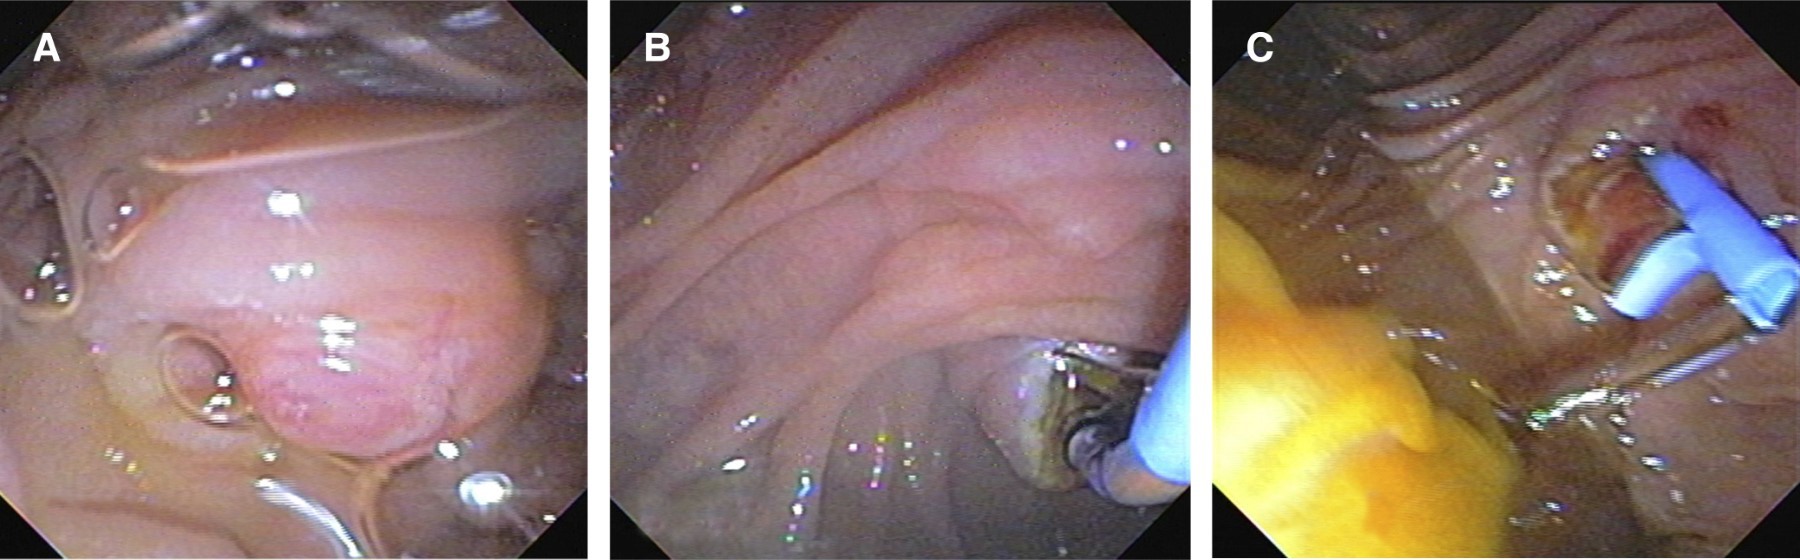

Durante el procedimiento quirúrgico se encuentra vesícula edematosa aumentada de tamaño con contenido purulento, pared engrosada de hasta 8 mm y segmentos de necrosis en su superficie, se observa dilatación del conducto cístico hasta 25 mm (Figura 2). Se procede a introducir duodenoscopio de visión lateral en tiempo transoperatorio hasta la segunda porción del duodeno, observando papila hipertrófica con ausencia de salida de bilis, se canula esfínter de Oddi en el primer intento y se opacifica de manera selectiva la vía biliar con medio de contraste observando dilatación importante de la vía intra y extrahepática, con colédoco tortuoso que llega a medir hasta 25 mm, por debajo de la unión de los conductos hepáticos derecho e izquierdo. En la unión del conducto cístico se observa una estenosis concéntrica de consistencia dura franqueable con la guía (Figura 3). Se realizan tres barridos con balón extractor obteniendo sólo detritus biliares con hemorragia al paso por el sitio de la estenosis. Se realiza cepillado biliar para ser procesado por patología y esfinterotomía de 20 mm, se decide colocar prótesis biliar Cotton-Leung® de 10 × 10 Fr y se retira la vesícula biliar (Figura 4).

Figura 2

Figura 4